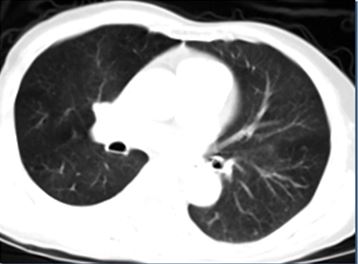

Hình ảnh CT ngực trước và sau điều trị

Trước điều trị                                 Sau 10 tháng

Trước điều trị: Hình ảnh u phân thùy giữa phổi phải. Kích thước 3 x 4 cm. Có nhiều nốt di căn ở cả hai bên phổi.

Sau điều trị: Đáp ứng gần hoàn toàn, u nhỏ đi nhiều và số lượng các ổ di căn hai bên phổi giảm nhiều.